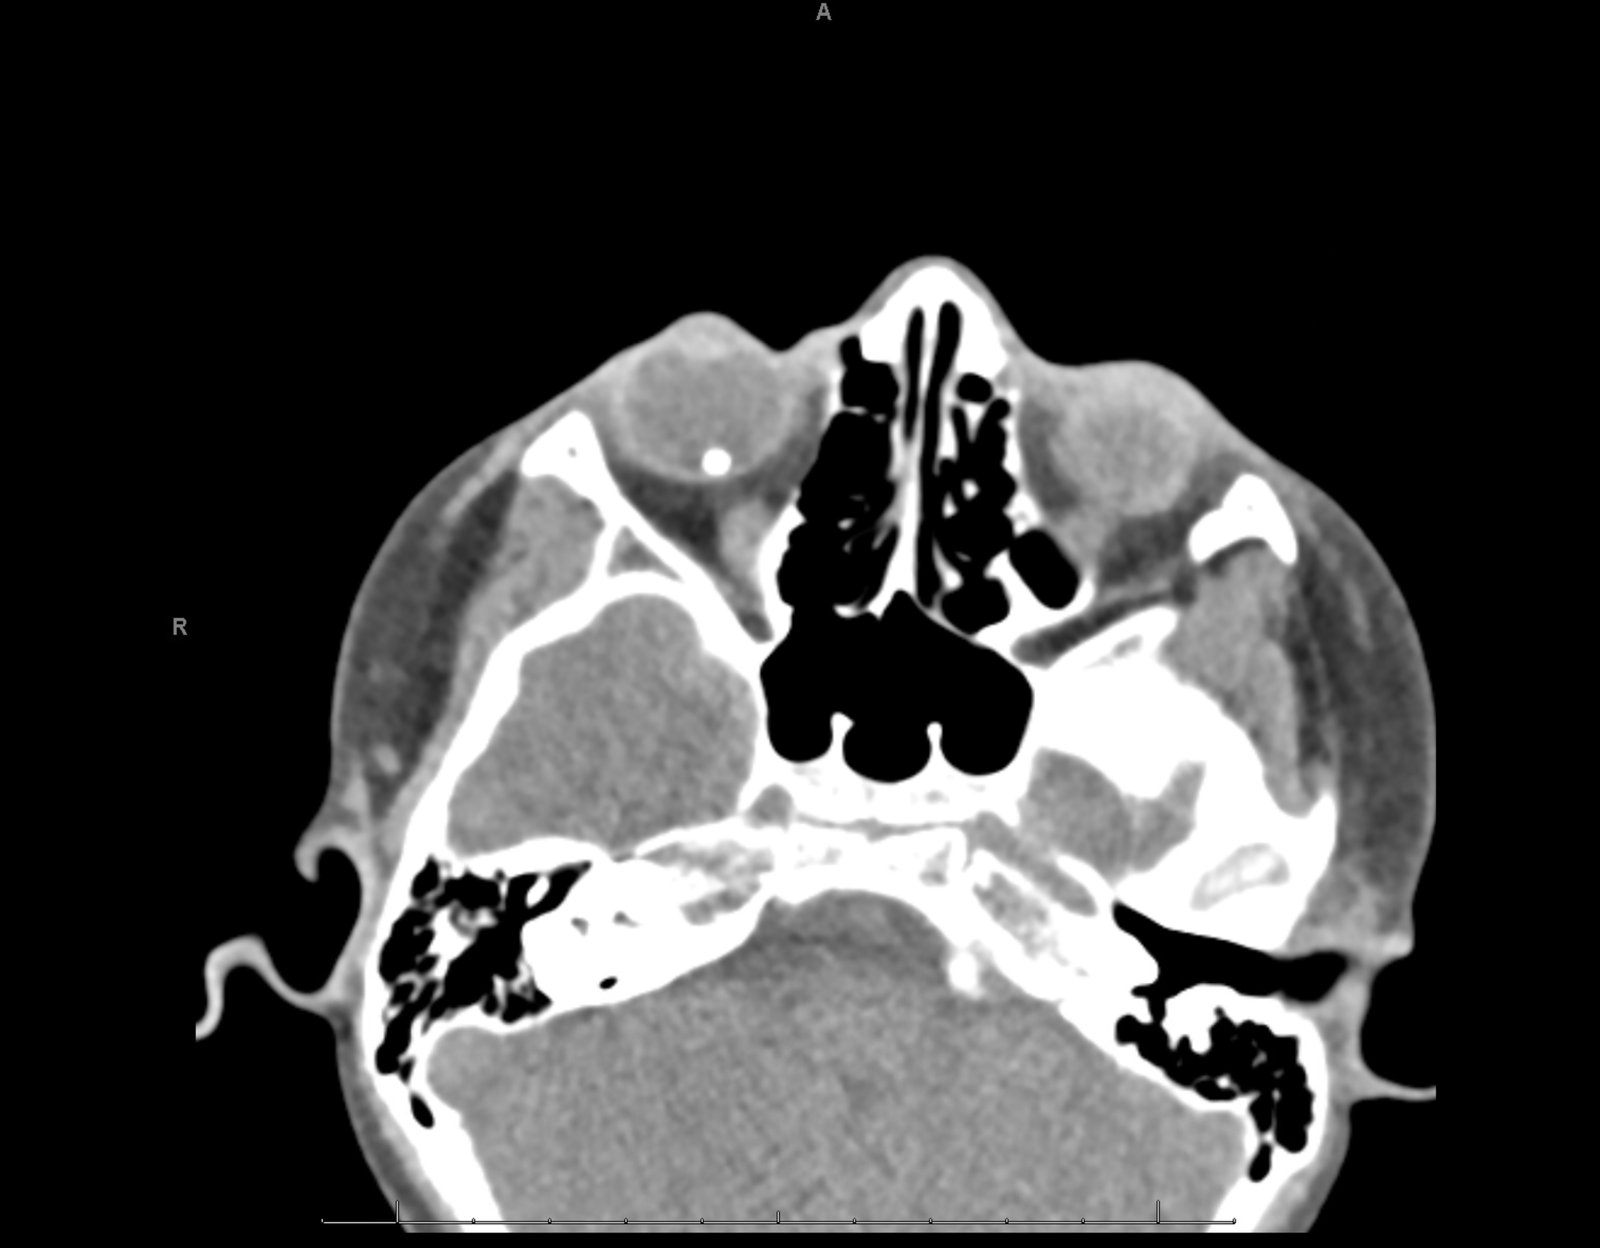

Computed tomography (CT) of the orbits was performed without contrast. There was a spherical high-density foreign body in the right posterior globe, inferiorly, at the 5 o’clock position measuring 3mm in diameter. No hematoma, lens dislocation, or significant decrease in volume was noted.